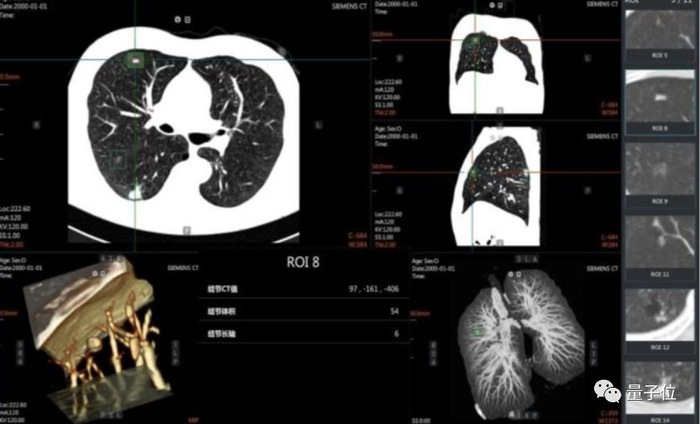

与此同时,这也强化了影像数据的积累和分析,也让基于 AI 的医疗影像分析 应用日趋走向成熟,一个过去需要10分钟进行筛查的肺癌前期诊断,在AI的加持下能够达到秒级,而且准确率也在95%以上。

目前,在医疗影像 AI 分析应用中,目标侦测神经网络正被广泛地运用,其通过深度学习的方法,能够对 X 光片、CT 成像等医疗影像进行高效、准确的病灶检测。

实战手册中,在与西安盈谷 Cloud IDT 智能应用、医学影像处理及分析云计算@iMAGES 核心引擎等相结合后,在肺结节诊断等一大批关键场景中建立起“AI+Cloud”的智能辅助诊断系统能力。